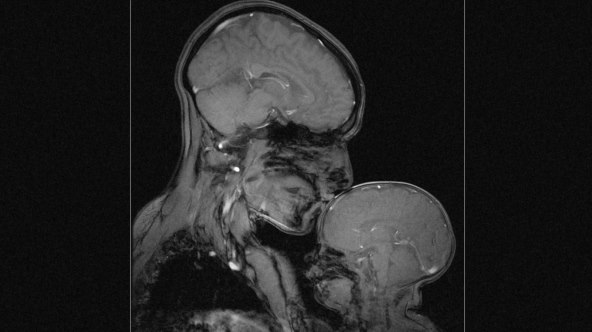

Neuroznanstvenica i profesorica Rebecca Saxe na istraživačkom sveučilištu MIT proučava ljudski mozak i njegovu sposobnost za razvoj misli i jezika. Ideja o zajedničkoj snimci s djetetom pala joj je na pamet već nakon prvog poroda no zbog kompleksnosti izvedbe, ta se zamisao ostvarila 2015. nakon rođenja njezina drugog sina Percyja.

'Bilo je zaista teško napraviti kvalitetnu snimku jer u uređaju za magnetsku rezonancu trebate biti potpuno mirni, a s malim djetetom je to gotovo nemoguće', komentirala je Rebecca, koja je nakon velikog broja neuspjelih pokušaja ipak uspjela uloviti trenutak. Snimku nije napravila u dijagnostičke svrhe već kako bi najpoznatiji portret na svijetu, onaj majke i djeteta, pogledala iz druge perspektive.

'Na ovoj snimci ne vidimo ni odjeću, ni frizuru ni boju kože. Ovo mogu biti bilo koja mama i dijete ili bilo koji tata i dijete u bilo kojem vremenu i dijelu svijeta. Ova slika budi univerzalne emocije ljubavi, ali i straha od ranjivosti i krhkosti koja je u nama', istaknula je Rebecca.